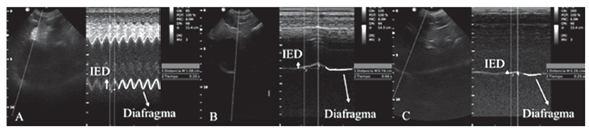

El operador registró los movimientos de la cúpula del hemidiafragma derecho, colocando la guía del modo M casi perpendicular al diafragma, se examinaron varios ciclos respiratorios registrando la amplitud de la onda (índice de excursión diafragmática en centímetros), tomado desde su punto máximo de elevación a la línea de base y el período de inicio de la onda hasta la mitad de su longitud de onda (tiempo inspiratorio en segundos) (Fig. 5 - 6), el cociente entre la excursión diafragmática (cm) y el Tiempo inspiratorio (seg) dio la velocidad de contracción diafragmática, variable calculada que también fue registrada.

Luego de evaluar la dinámica del diafragma con ultrasonido en modo M, el límite inferior del índice de excursión diafragmática del domo del hemidiafragma derecho se estimó en perros internados fue 1,45 mm, no se encontró diferencia estadísticamente significativa en la evaluación en las diferentes posiciones en perros sanos y anestesiados del índice de excursión diafragmática, tiempo inspiratorio y velocidad de contracción diafragmática. Al comparar los perros para la medición del índice de excursión diafragmatica DLD (decúbito lateral derecho) y DD (decúbito dorsal), se observaron diferencias significativas (p<0,01), siendo el valor menor en los perros anestesiados (Fig. 9). Hubo algunas limitaciones en este estudio; no se evaluaron perros sanos, sino perros internados en los cuales puede existir disfunción diafragmática oculta, que afecte la medición del índice de excursión diafragmática, los cuales pueden influir sobre los resultados encontrados. Los perros internados y anestesiados no se sometieron a pruebas de función cardiopulmonar. Se utilizó G-FAST para definir el estado cardiopulmonar normal. Los resultados no indican necesariamente una función cardiopulmonar normal, por eso no se descarta que los perros internados y anestesiados tengan algún grado de disfunción diafragmática o lesión cardiopulmonar primaria o secundaria que pueda alterar la medicion del ìndice de excursión diafragmática, otra de las limitantes del estudio fue que solo se tuvo en cuenta el valor de la medición del índice de excursión diafragmática de la cúpula del hemidiafragma derecho y no la del izquierdo, por la dificultad en la visualización de la ventana generada por la posición anatómica normal del estómago y el bazo. La difusión diafragmática puede ser una de las complicaciones que generan un desafío frecuente en cuidados intensivos y perros post quirúrgicos (Beal et al., 2001), ya que puede permanecer oculta generando una falla ventilatoria mecánica, la cual puede ser primaria o secundaria teniendo en cuenta las múltiples causas que la pueden provocar como el SDRA (síndrome de diestress respiratorio agudo), neumonía, dolor, fiebre, ETC. Se ha reportado en perros post quirúrgicos de la columna cervical como slot ventral (Rossmeisl et al., 2013), cirugía torácica y movilización de la arteria mamaria interna. También se reportan lesiones indirectas por separadores del esternón o mal uso de dispositivos de electrocauterio (Raillard et al., 2017). Todas estas pueden generar una injuria mecánica del nervio frénico y como consecuencia la lesión diafragmática y el fallo ventilatorio. Es por esta razón que el uso de una herramienta portátil y practica para el monitoreo de la ventilación como el ultrasonido cobra importancia en la aplicación de estos casos y escenarios como la médica interna, urgencias, radiologia, anestesia, cirugia y los cuidados intensivos. El efecto de los fármacos que se usan para la premedicación e inducción de los perros sometidos a cirugía electiva, sobre el sistema cardiorrespiratorio, comúnmente se evalúa de acuerdo con sus signos vitales, la frecuencia cardiaca, la frecuencia respiratoria, So2%, la presión arterial (Kennedya y Smitha, 2015). La medición del índice de excursión diafragmática mediante ultrasonido muestra una gran ventaja en la detección temprana de alteraciones en la movilidad del diafragma, permitiendo evaluar en tiempo real cambios generados esperados como la apnea posinduccion (PIA), generada por el aumento en la velocidad de infusión de los medicamentos y así, el aumento de la concentración en sangre y cerebro (Bigby et al., 2017).